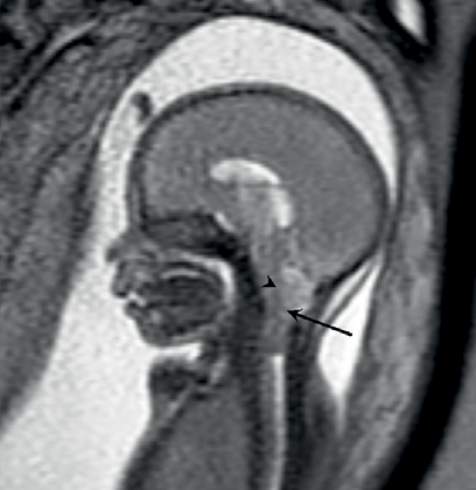

Mri Scans More Precisely Define And Detect Some Abnormalities In Unborn Babies Great Ormond Street Hospital